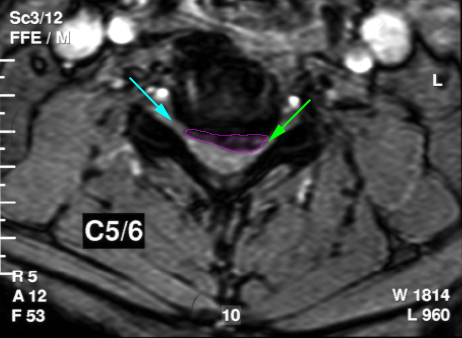

Κήλη αυχενικού δίσκου, επίπεδο Α5-Α6, με στένωση του νευρικού τρήματος (πράσινο βέλος) και πίεση του εξερχόμενου νεύρου. Ελεύθερο τρήμα με κυανό βέλος. |